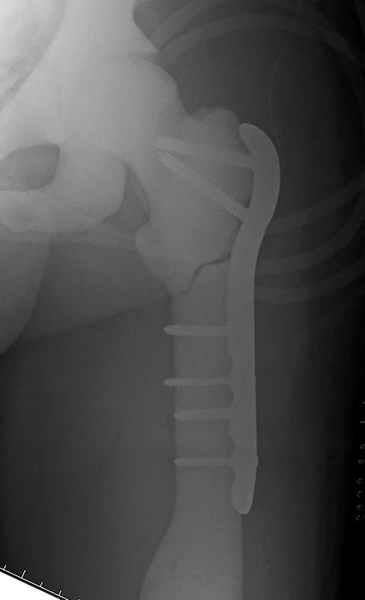

После неудачной попытки скелетного вытяжения в первом мед.учреждении, после осмотра снимков и изучения истории, поставили диагноз “Остеопетроз” или мраморная болезнь, редкая наследственная костная паталогия, где имеется нарушение формации остеокластов.

Конечно, было бы идеальным применение интрамедуллярного остеосинтеза, но учитывая прежний собственный опыт (лечил перелом бедра) и

публикации, предупреждающие о трудностях при обработке кости (иногда из-за неподготовленности инструментария результатом была неадекватная фиксация перелома, или перенос операции из-за фактора усталости оперирующего персонала), решили применить пластину (и в этом же случае был выбран Synthes plate, так что представитель за два дня

Заказаны были дополнительные различные дрели, и на следующий день, усиленной бригадой, больного прооперировали, потратив на каждое отверстие около 25-35 минут, хотя сверлили с охлаждением по нарастающей по диаметру сверл и с их заменой каждые 2 мм сверления.

Теперь стоит задача со сращением перелома, из-за отсутствия литературных данных по применению костных стимуляторов при остеопетрозе, и не зная как поведет в этой среде Grafton, все таки надеюсь, что даст толчок к стимуляцию, решил применить пастообразную деминерализованную костную матрицу, расположив спереди между отломками.